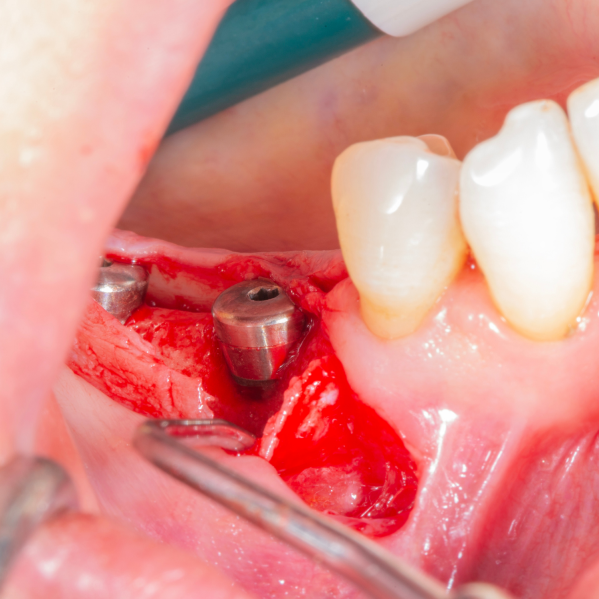

Diş çekiminin yıllar önce yapılmış olmasına bağlı olarak ince kemik varlığında implant ve kemik grefti uygulandı.